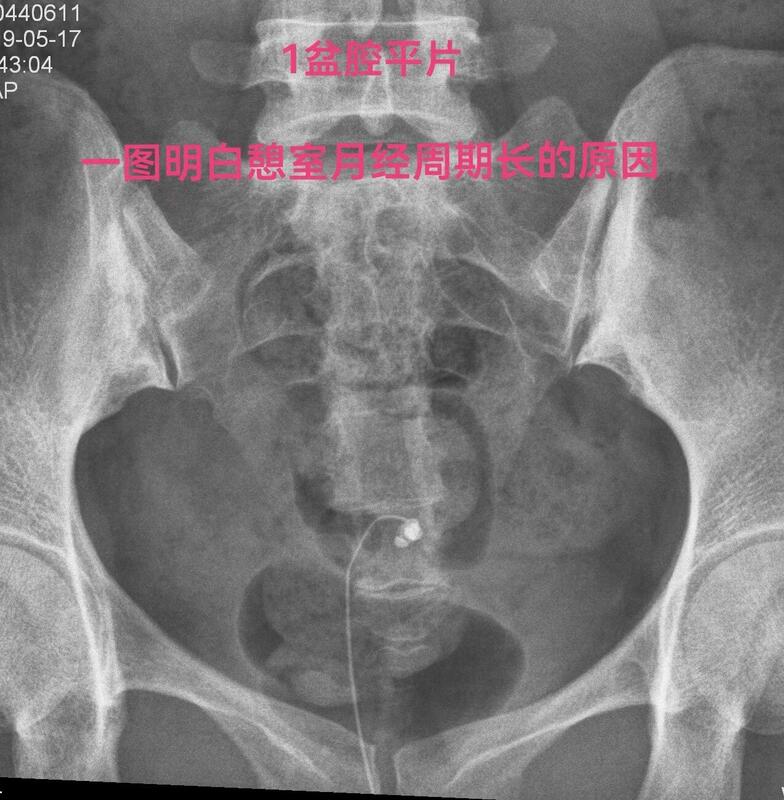

下面一例造影图就可以看直观看懂憩室导致经血流出不畅

弥散相子宫腔内造影剂完全流出来了,憩室内还有较多造影剂充满憩室腔。月经血流出相仿。